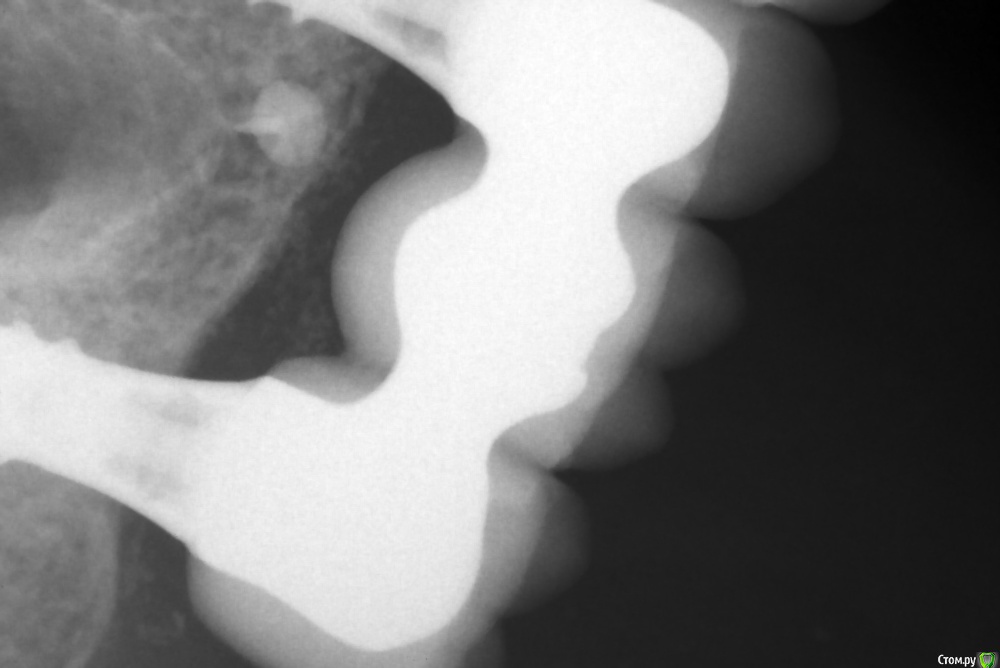

Хирургический план :  консервативное лечение у ЛОР специалистов

1) имплантация в позиции 15,17 з с закрытым синусом и незначительной НКР